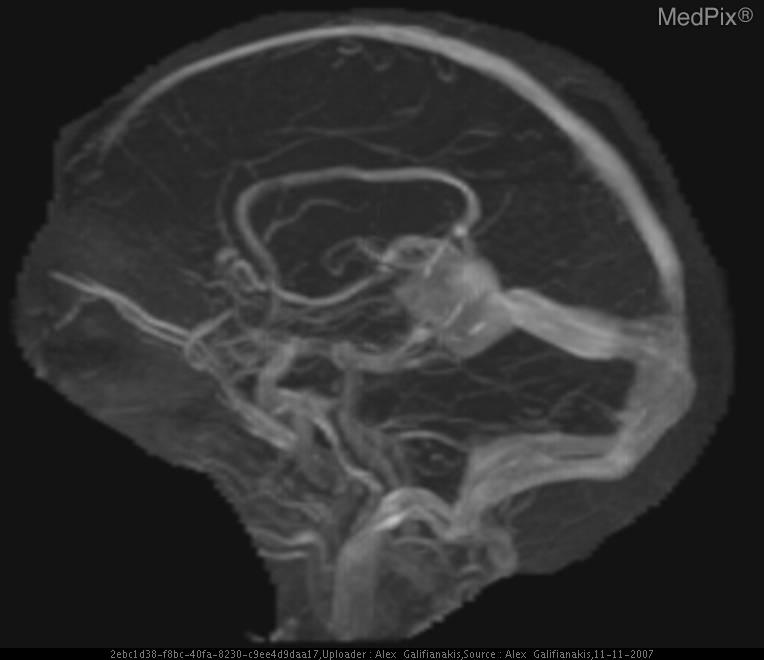

лизация мальформации

Эмболизация мальформации 113 фотографий